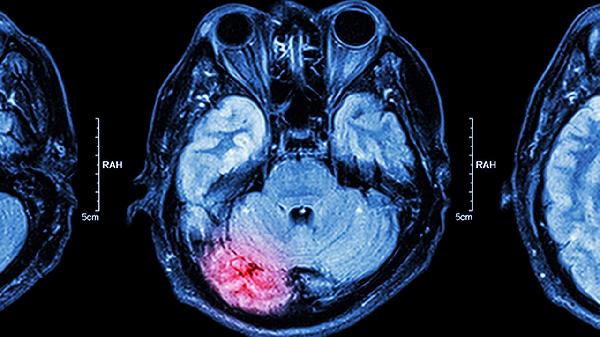

腦硬膜下血腫保守治療的恢復(fù)時間因個體差異而存在變化,通常輕微的血腫在嚴格遵醫(yī)囑、定期復(fù)查的情況下,可能需要數(shù)周至數(shù)月的時間才能完全吸收并恢復(fù)健康。恢復(fù)的具體時間取決于血腫的大小、位置、患者的身體狀況,以及治療階段的配合程度。

血腫的大小和性質(zhì):小血腫(厚度小于10mm)且沒有明顯臨床癥狀的患者更適合保守治療。如果血腫較小,并且沒有隨著時間變化擴大,那么通常血腫會逐漸被吸收,可能需要幾周至幾個月時間。

影像復(fù)查:定期進行頭顱CT或MRI復(fù)查是必要的,用于動態(tài)觀察血腫是否縮小或擴大。如果血腫吸收緩慢或擴大,可能需要調(diào)整治療方案。